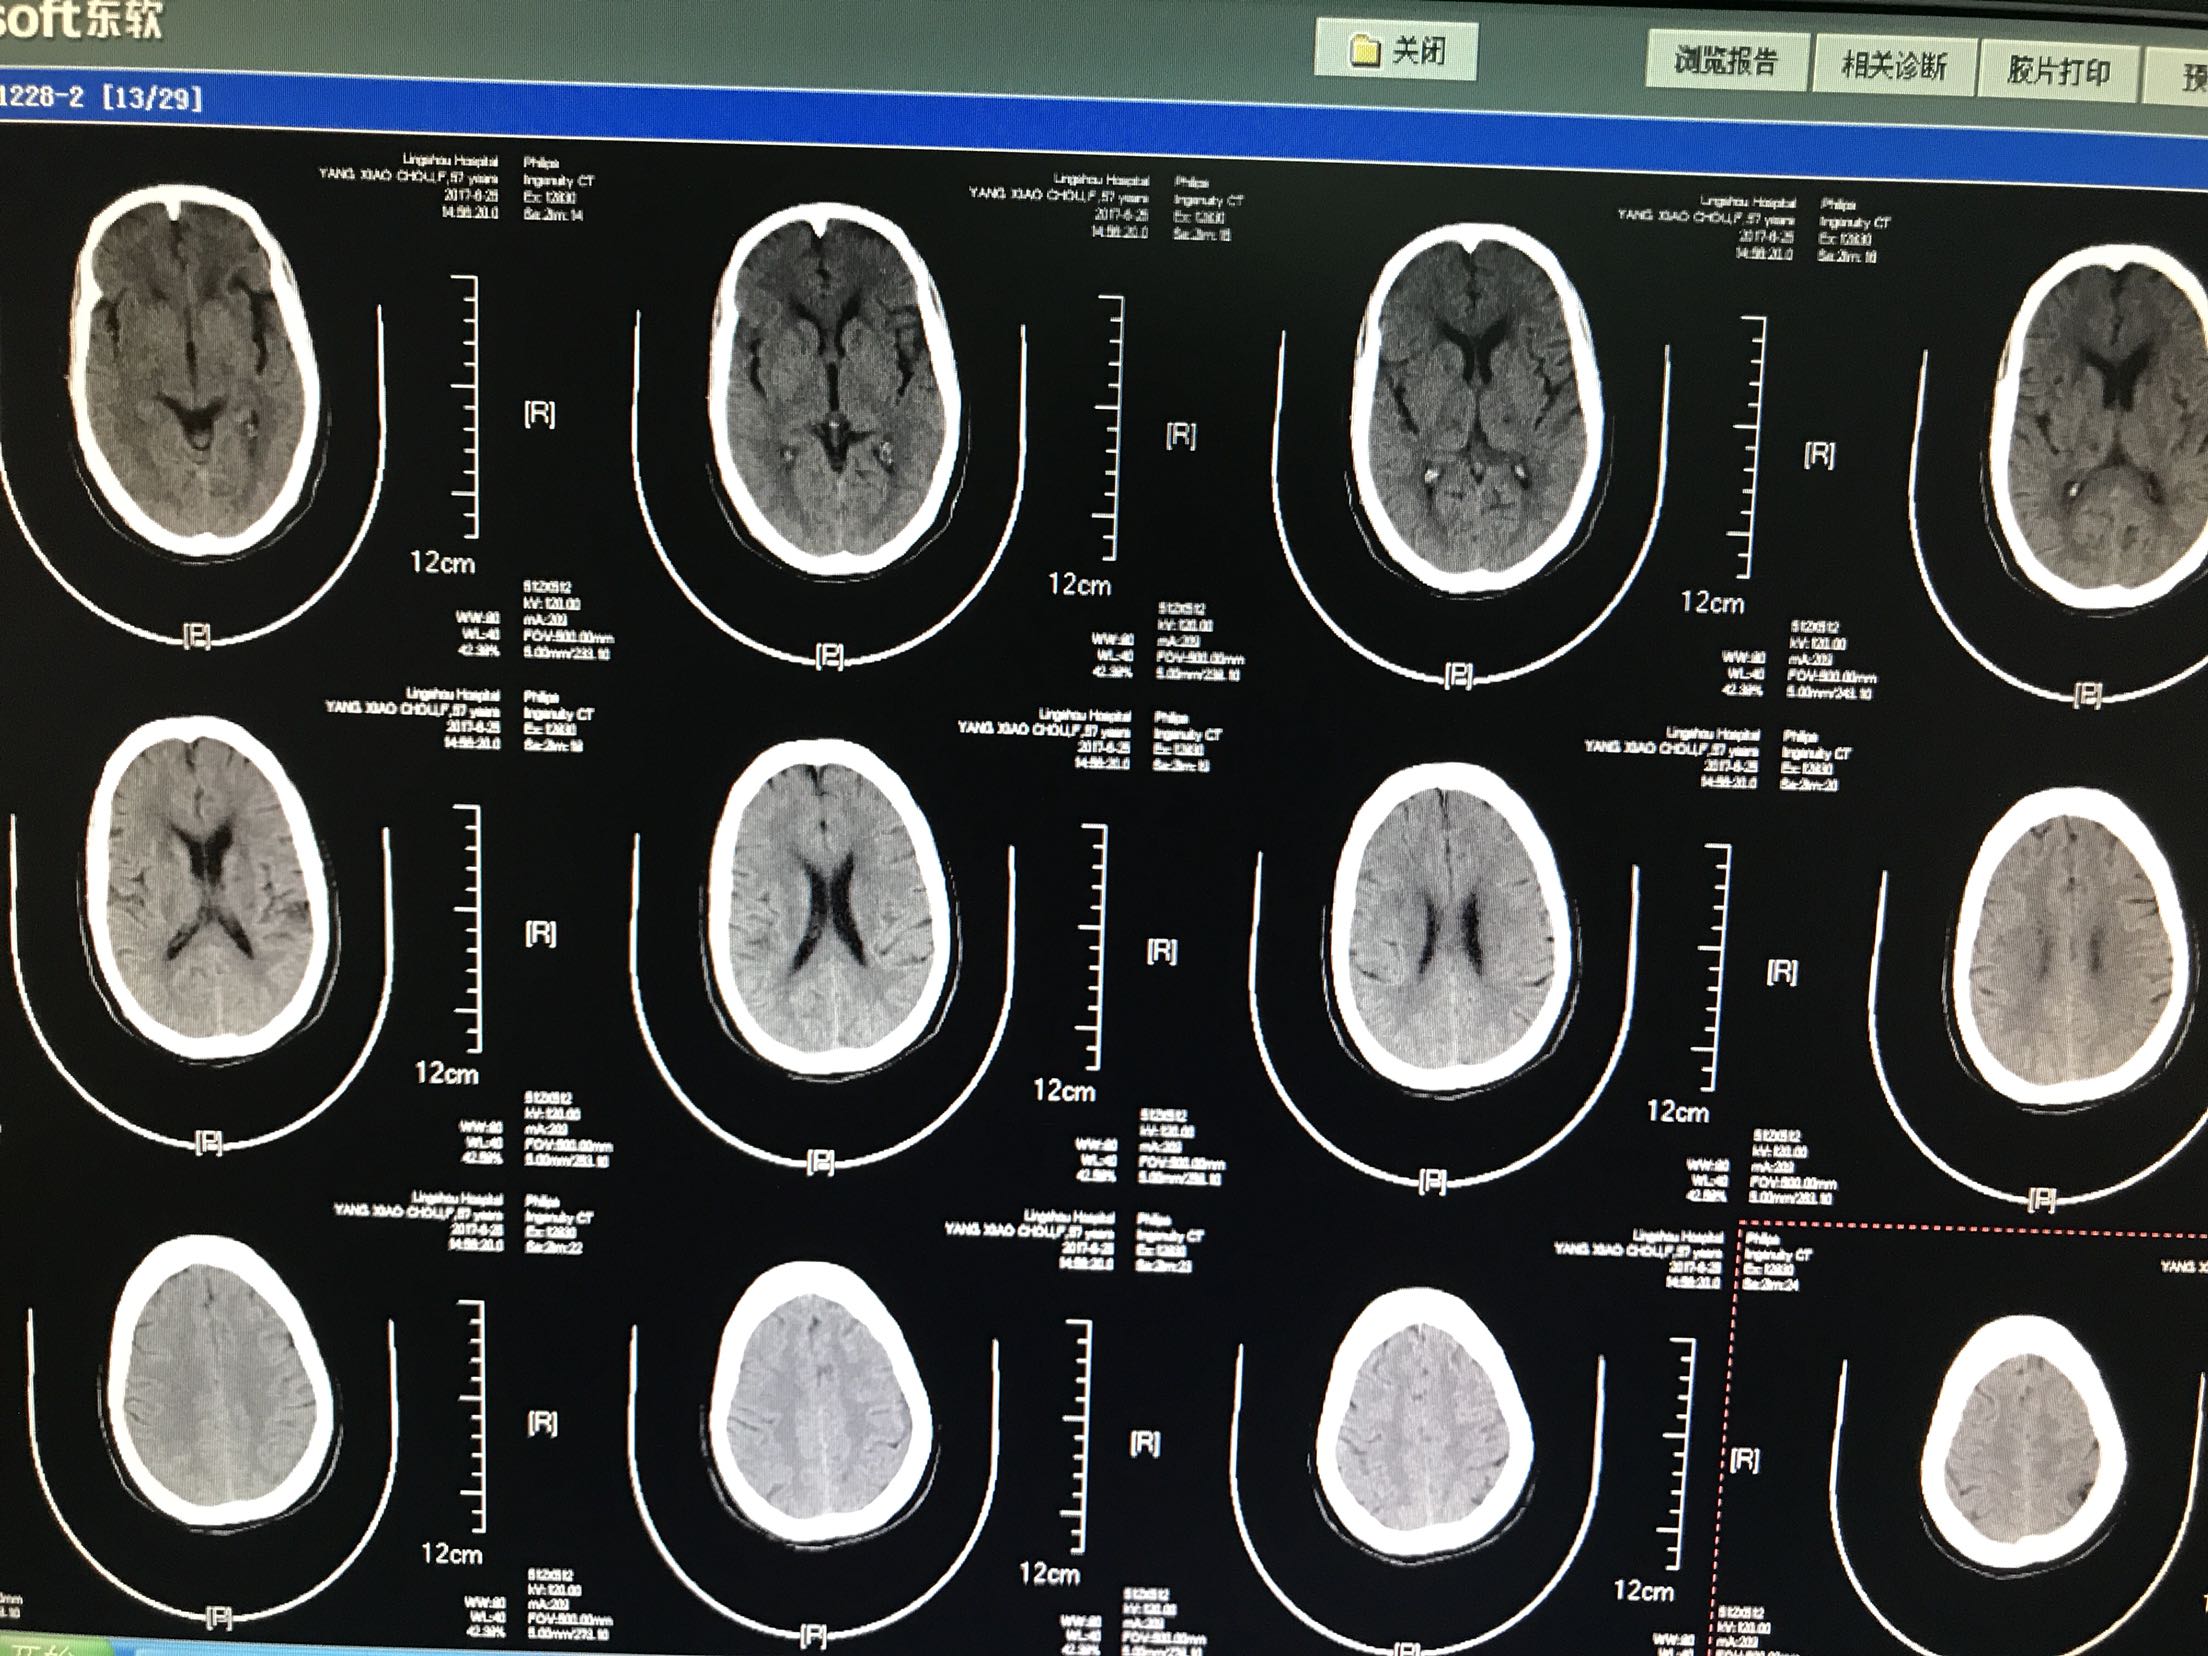

患者主因言语不利,右侧肢体无力2小时入院,患者中年男性57岁,既往"高血压,脑梗死"病史,未留明显后遗症,未监测血压,患者入院前2小时无明显诱因出现言语不利,右侧肢体无力,听理解无障碍,上肢不能抬举,下肢不能负重,伴左侧头痛,无头晕,恶心,呕吐,无饮水呛咳,急诊急查头CT:脑干出血,心电图示:房颤,为进一步治疗收住院

1.脑干出血2.房颤,药物给于止血,脱水降颅压等治疗,密切观察意识变化

脑干出血比较凶险,多预后差,应该密切注意生命体征。